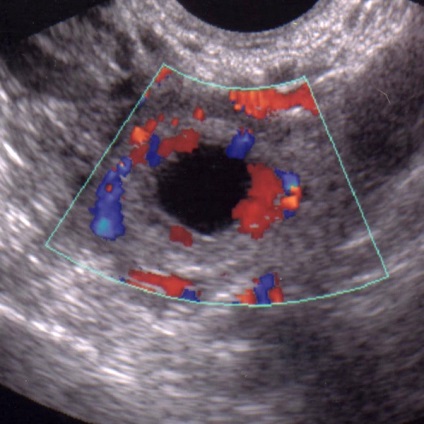

Ha egy nő aggódik a fenti tünetek, akkor forduljon orvoshoz, és mindent megmagyarázni neki. Végzett ultrahang, amelyben az orvos, és hiányzik az embrió vagy a felfüggesztés a fejlődés. És a tünetek hiányában a nők, ő megtanulja anembrionii a következő vizsgálat ultrahang készülék, ha az orvos észrevette a különbség a petesejt és embrió.